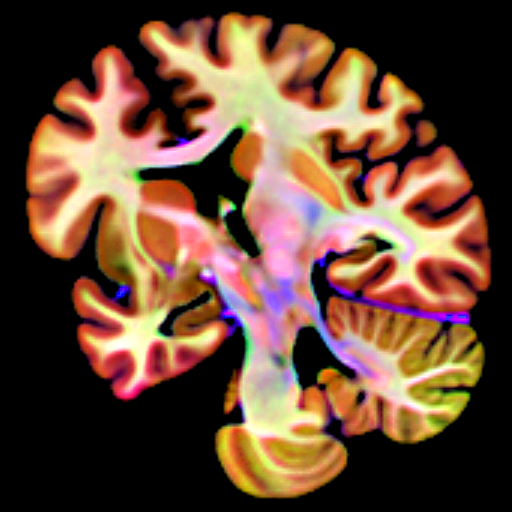

Using MRI, we research the neuropathology of MS associated with progression and hard to treat with current medications, including cortical demyelination, smouldering MS lesions, and leptomeningeal enhancement.